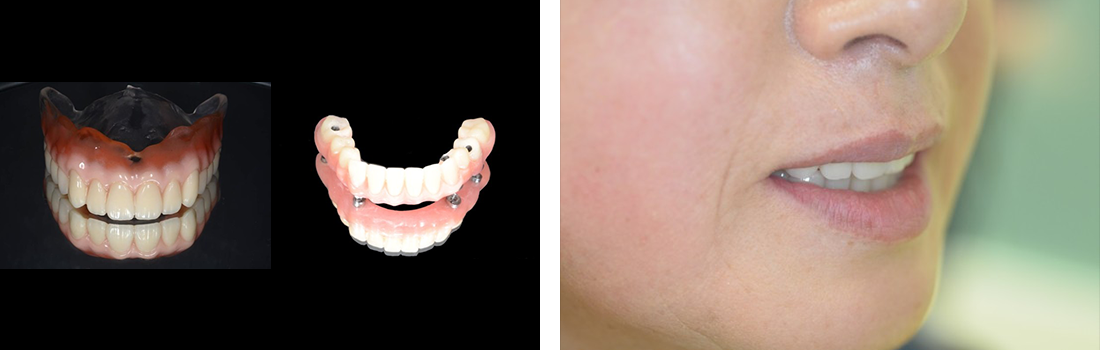

All-on-4症例 Case1

Treatment cases

Before

After

インプラント治療は、咀嚼機能の改善だけでなく、 口腔周囲筋の発達により見た目の若返りにも貢献してくれます。